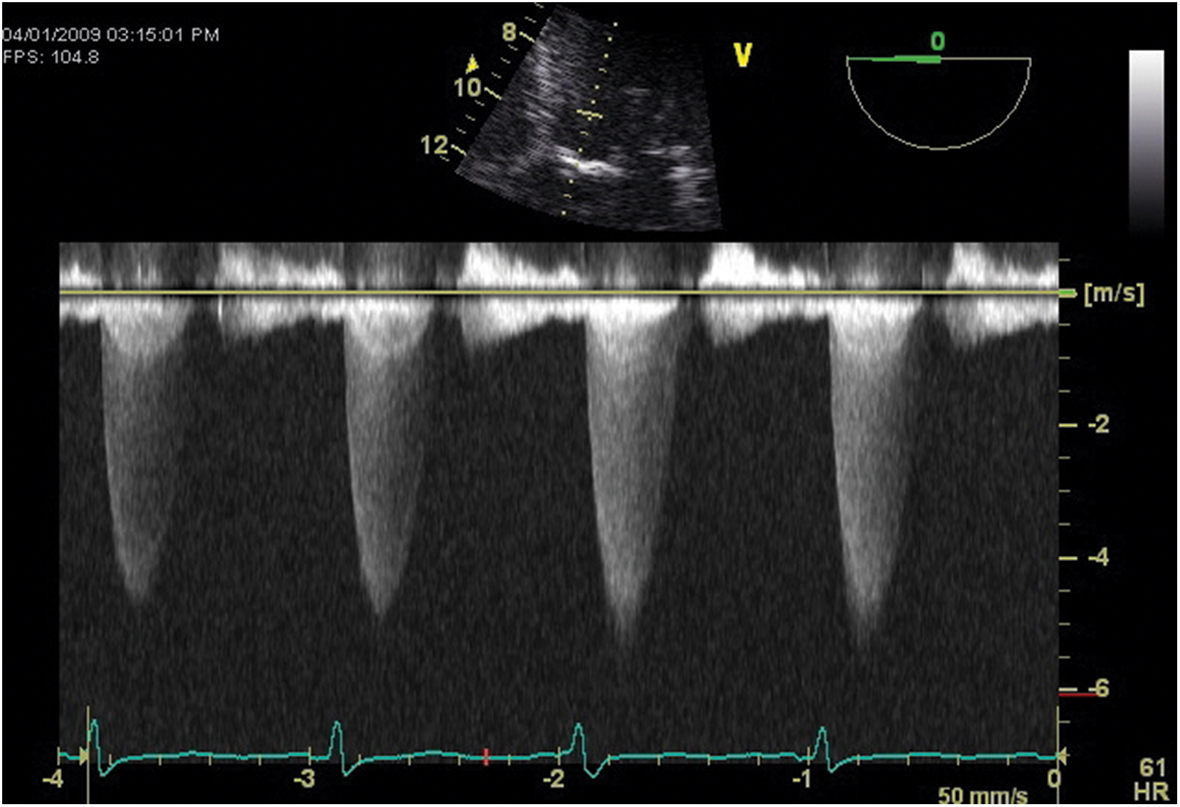

Pressure gradients are derived through analysis of the Doppler profiles of blood flow. A commonly determined echocardiography gradient is that from the LV to the aorta in the setting of AS. To obtain the change in blood flow velocity across the AV with TEE, the probe is advanced far into the stomach and sharply anteflexed and left deflected to obtain the window from the apex of the heart (deep transgastric long axis [LAX]) and align the ultrasound beam most parallel to the path of blood flow. From this window, the continuous-wave Doppler cursor is directed across the left ventricular outflow tract (LVOT) and AV. An example of such a spectral Doppler display is seen in Figure 7.14. The large increase in blood flow velocity in this display occurs at the narrowest point along its path, which, in this case, is the stenosed orifice of the AV. Using the modified Bernoulli equation, a gradient is calculated (100 mm Hg in the example). This represents the maximum instantaneous systolic pressure difference between the LV and the aorta. AS is also quantified at the time of catheterization by measuring the pressures from within the LV and the aorta as a rapid response pressure transducer catheter is withdrawn from the LV back to the aorta across the stenotic valve. The standard pressure gradient from direct measurements is the difference between the maximum LV and aorta pressures, or "peak-to-peak" gradient. Figure 7.15 illustrates that these peaks are not simultaneous events. Therefore, Doppler-derived AS gradients are usually higher than those derived by left heart catheterization.

Figure 7.14.: Continuous-Wave Doppler Across the Aortic Valve in the Deep Transgastric Apical View from a Patient with Severe Aortic Stenosis.

Continuous-wave Doppler across the aortic valve in the deep transgastric apical view from a patient with severe aortic stenosis.